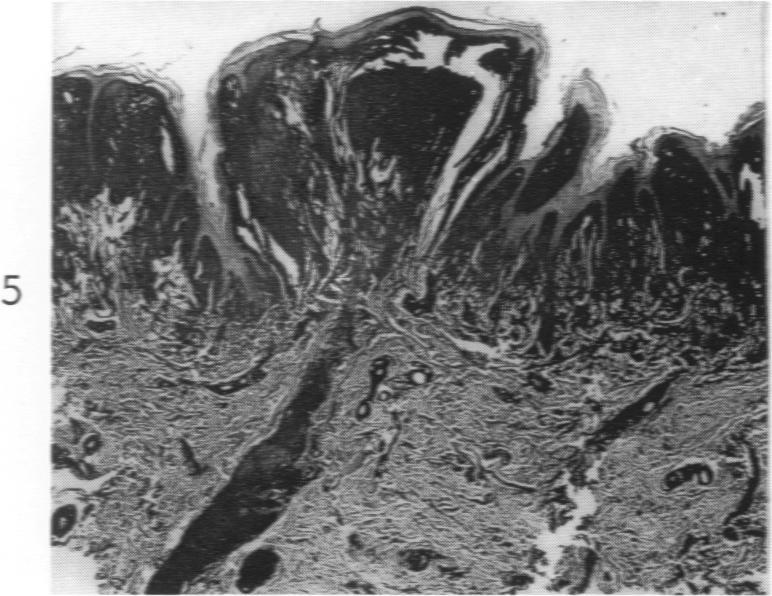

Lipoid Proteinosis (Lipoglycoproteinosis): A Histochemical Study of Two Cases.

Am J Pathol. 1962 May;40(5):599-613.